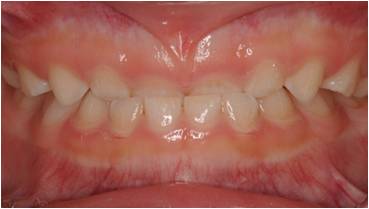

治療前

受け口の小児矯正治療(7歳の女子)の治療前後の写真です。矯正治療によって下顎前突(受け口)と上顎の狭さが改善され、正しい咬合に導かれています。